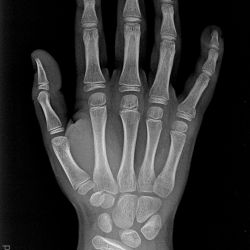

Aitken 1 Fraktur